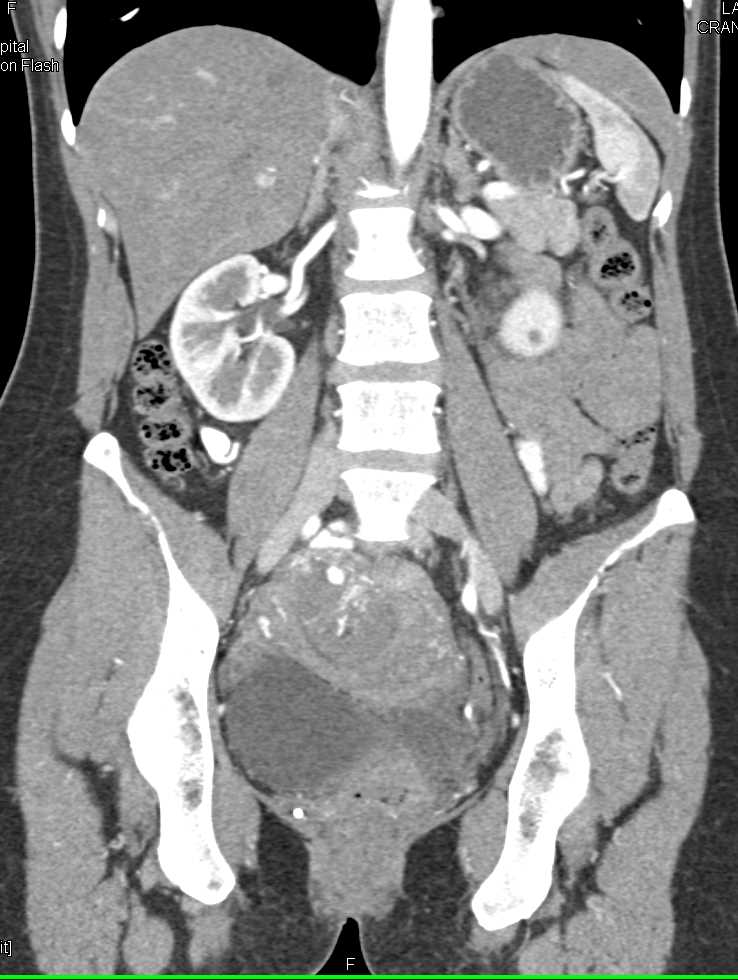

Theca Lutein Cyst on the Left